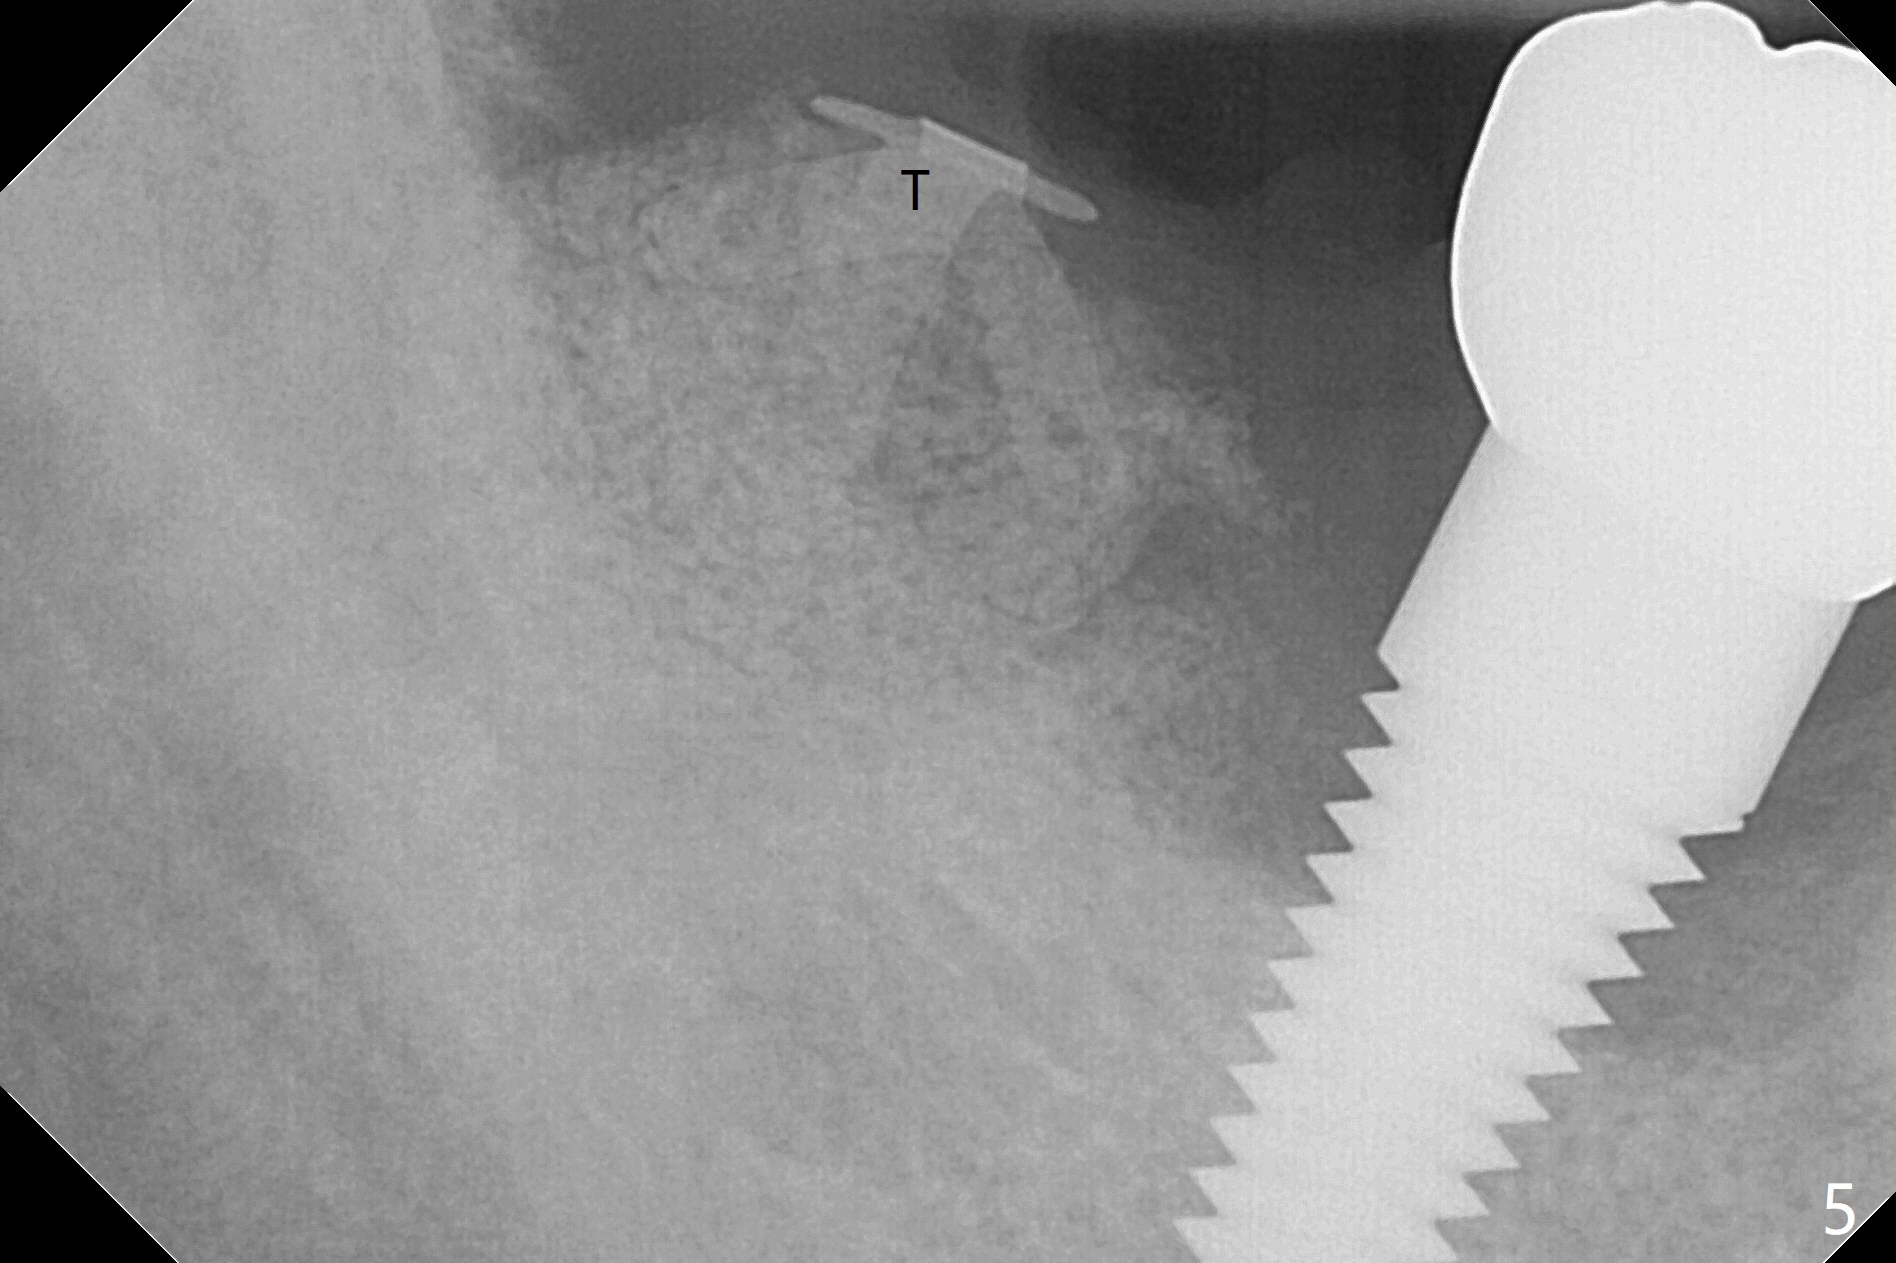

A 67-year-old man returns for periodic exam and #19 impression (Fig.3), which is impossible because there is open bite on the left (Fig.1 *). The latter is related to several periodontal abscesses (supraeruption, Fig.1,2). His chief complaint is mobility of #31 (Fig.3,4). Due to severity of infection, #31 is extracted with bone graft retained by Titanium-Reinforced Membrane (Cytoplast, Fig.5 T). PTFE suture is used. It is easy to tie knots with this non-resorbable (absorbable) suture. The Titanium-Reinforced Membrane exposes 1.5 months postop (Fig.6), which makes its removal easy (Fig.7). In fact the patient is pre-diabetic.